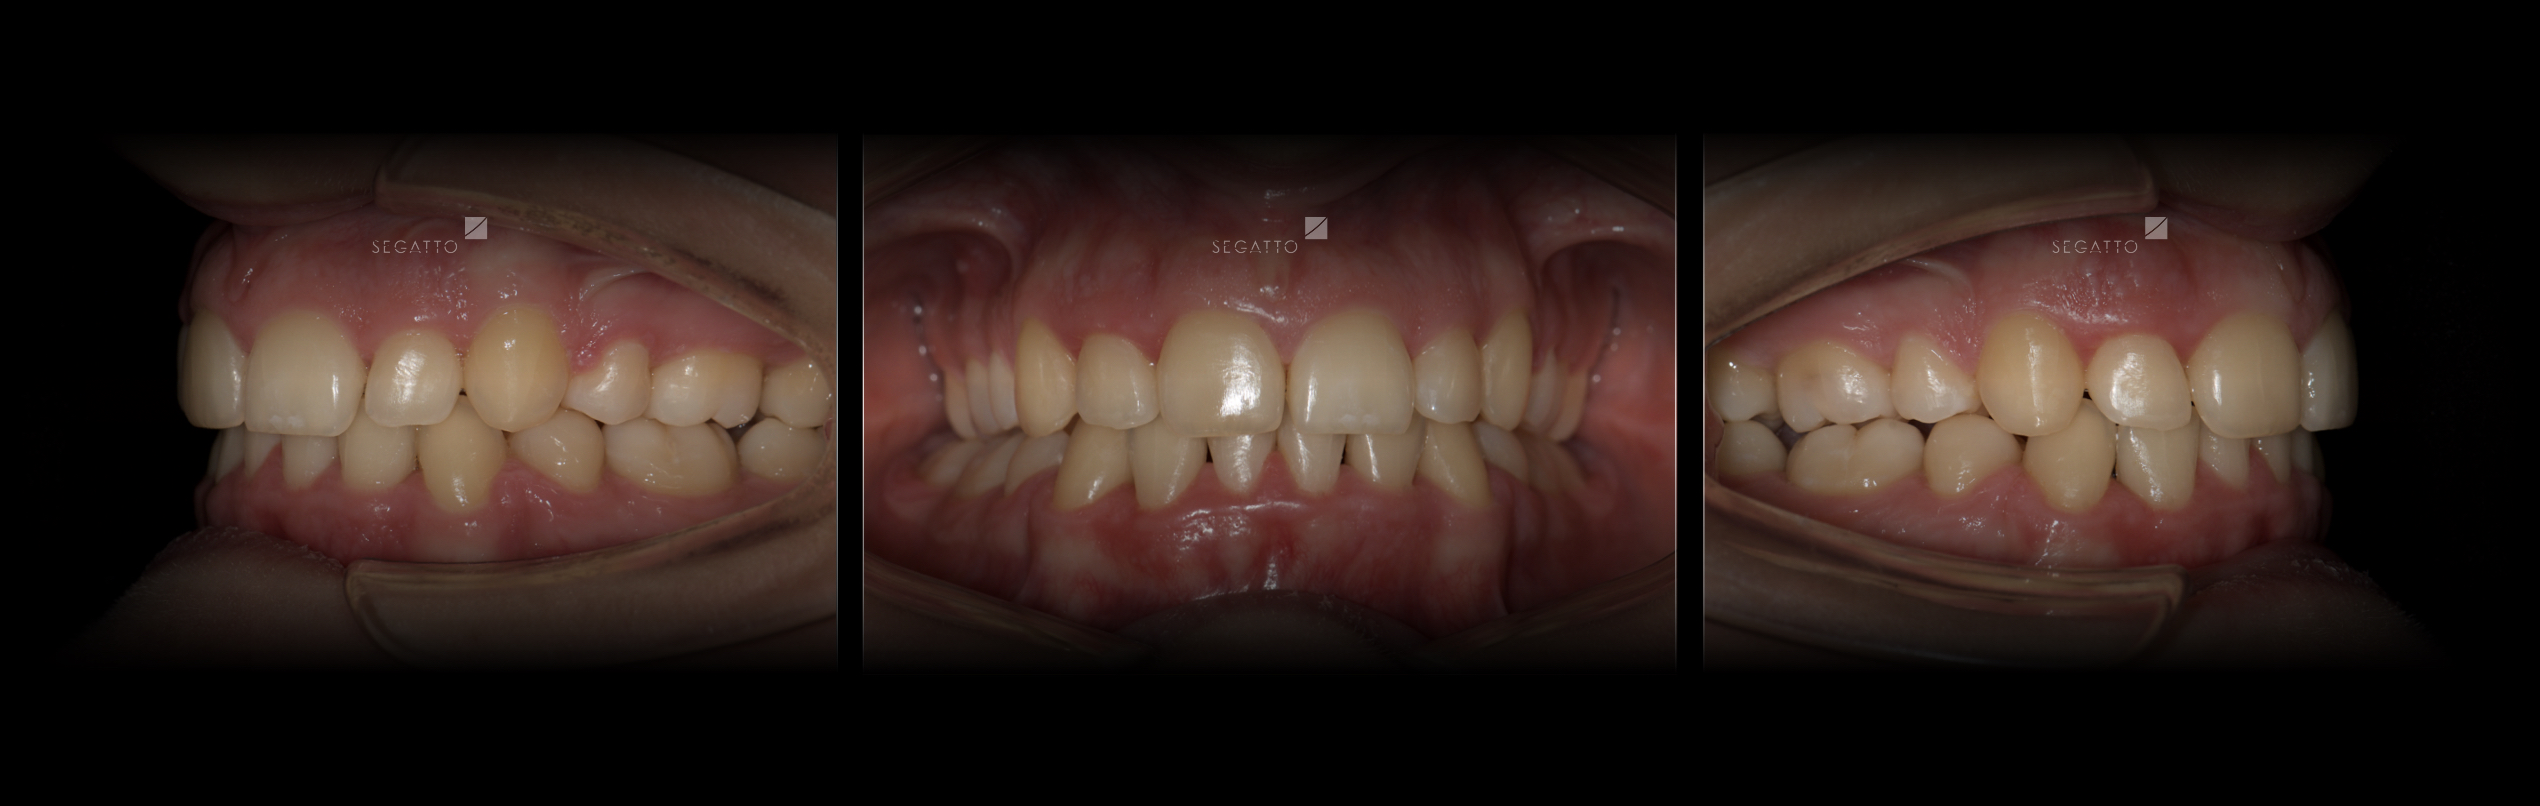

Orthodontics

Cases